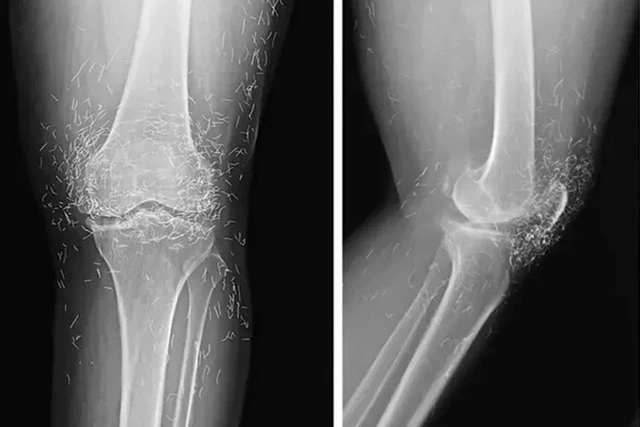

Rentgen müayinəsi zamanı sümüklərin qalınlaşması və deformasiyası, osteoartritin tipik əlamətləri, eləcə də diz oynağının ətrafındakı toxumaya yerləşdirilmiş yüzlərlə qızıl fraqmentlər müəyyən edilib.